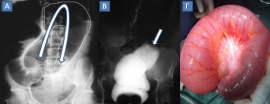

Αποτελεί τη συστροφή του εντέρου γύρω από τον άξονα του μεσεντερίου του και αφορά συχνότερα το σιγμοειδές (65%) και το τυφλό. Οι καταστάσεις που προδιαθέτουν σε συστροφή σιγμοειδούς είναι: (1) πλεονάζον, μεγάλου μήκους σιγμοειδές, (2) μακρύ μεσοσιγμοειδές με στενή βάση και (3) υψηλό φορτίο κοπράνων λόγω βαρείας, χρόνιας δυσκοιλιότητας. Συχνότερα…